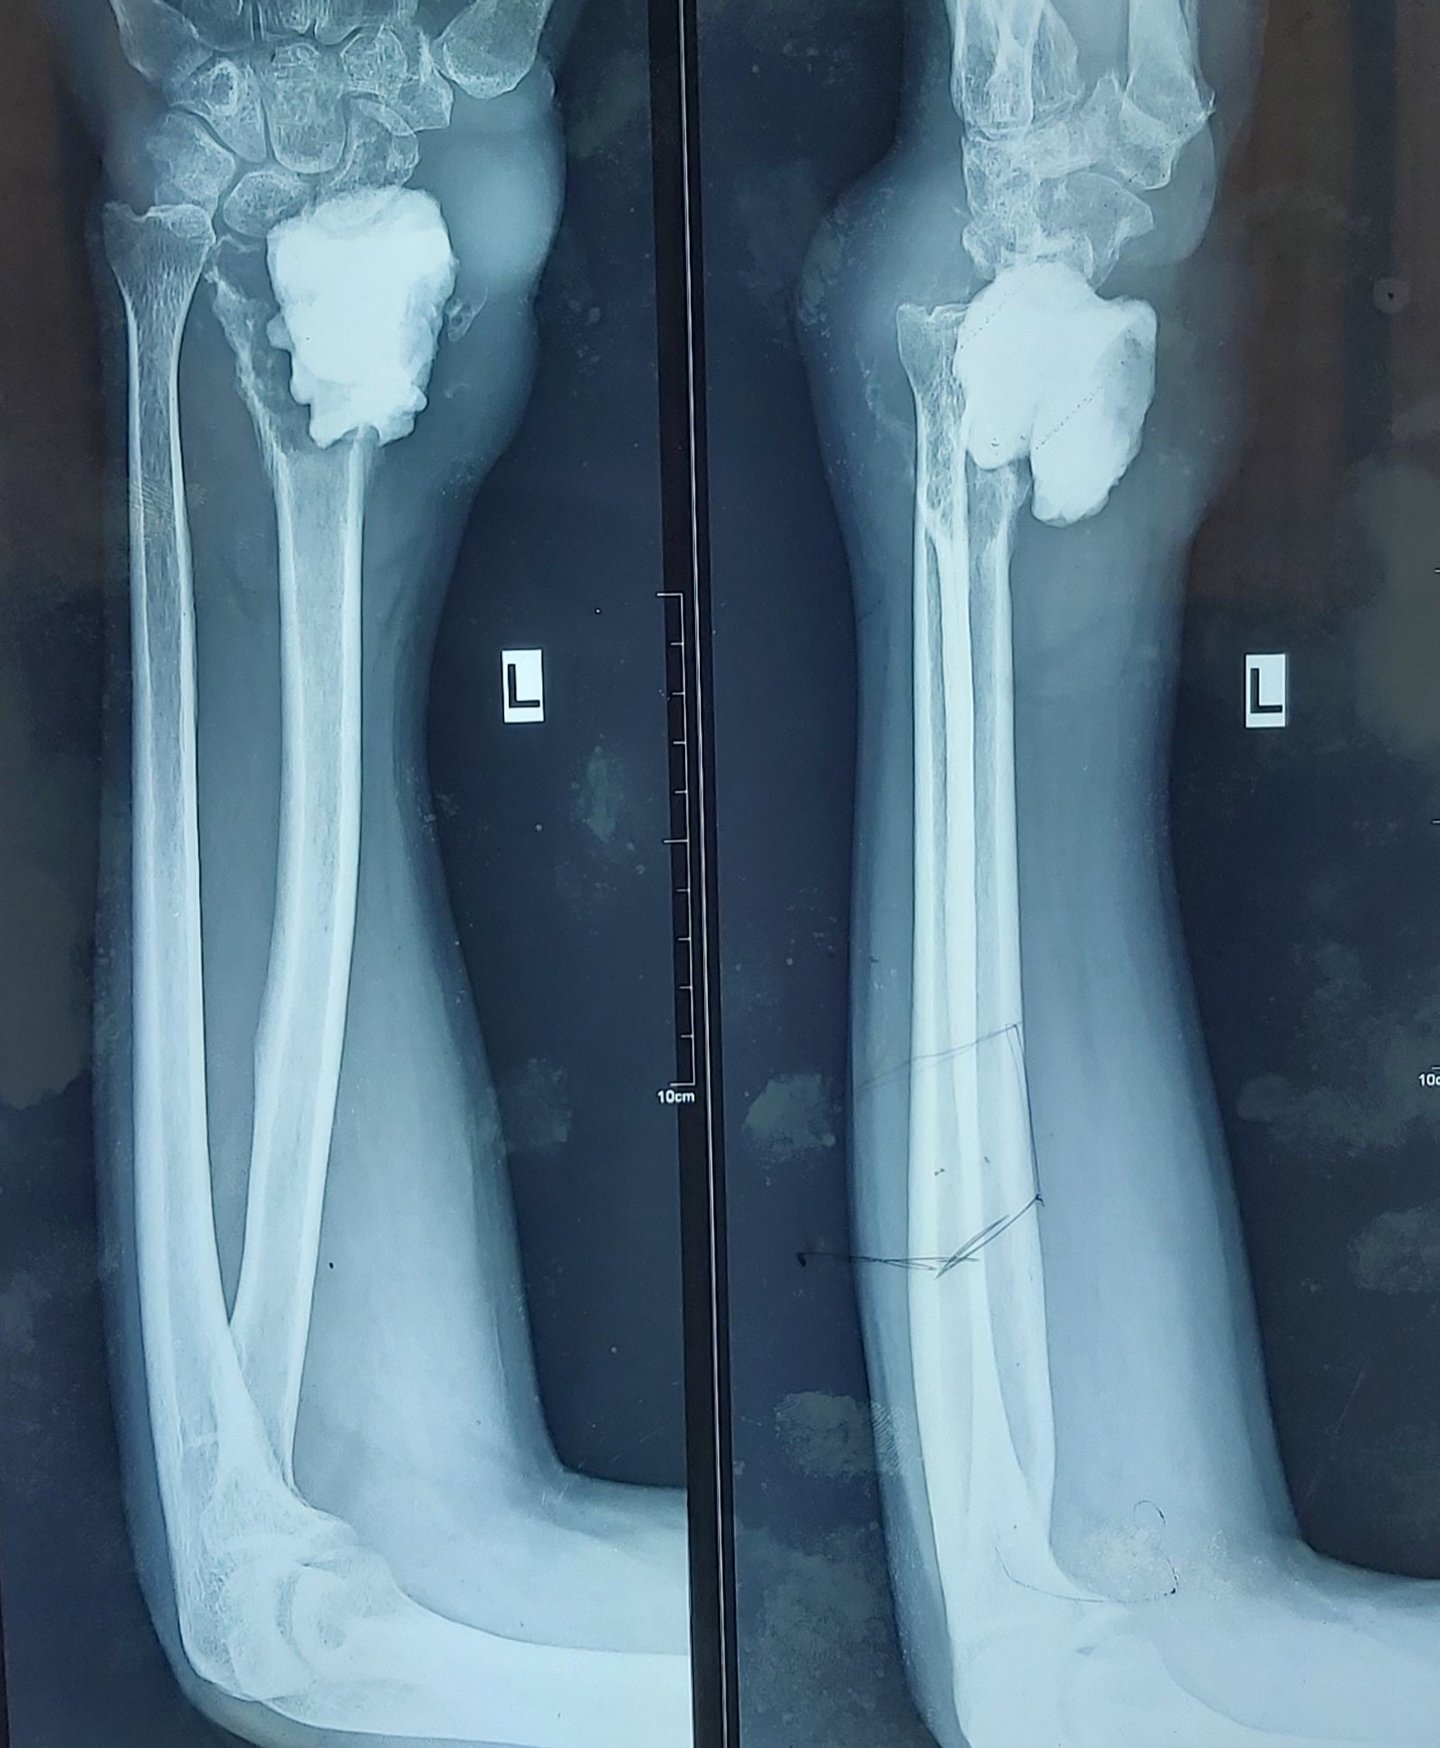

Management of Paediatric Proximal Tibia Osteosarcoma - A Novel Technique of Preservation of Physeal Growth

Osteosarcoma is a malignant tumor, the treatment of which is controversial between amputation and limb salvage surgery. Osteosarcoma occurring in a child is a challenge to manage due to the arrest of limb and the resultant limb length discrepancy. The management options for a child less than eight years of age are very limited.